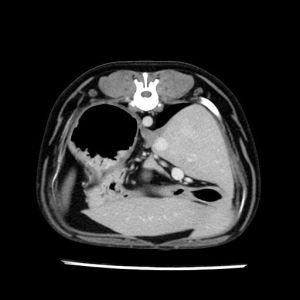

La lesione focale epatica , la ceus,la Tac e il chirurgo .